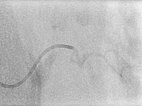

Auch in der Übersichtsangiographie über die linke Arteria iliaca externa zeigt sich keinerlei Perfusion des Tumors mehr, die Tumorvaskularisation ist somit erfolgreich superselektiv vollständig verschlossen. Alle nicht pathologischen Arterien sind erhalten.